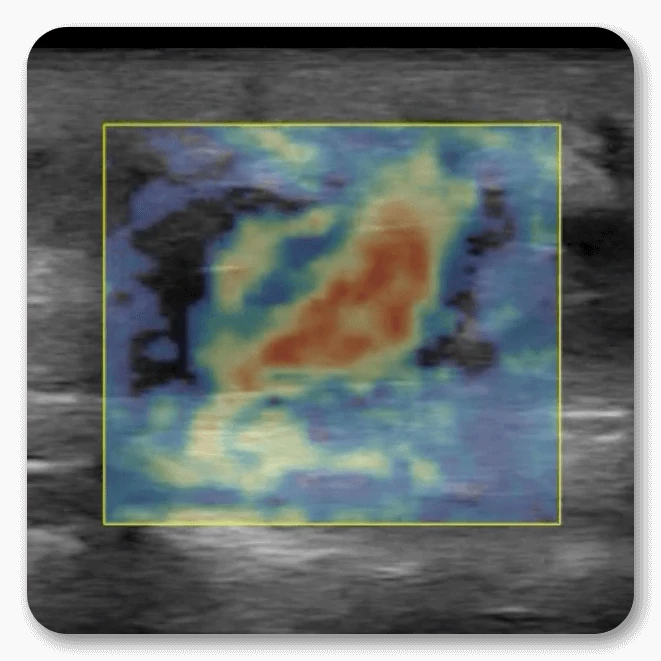

Strain Elastography

Strain Elastography allows for the visualization of stiffness differences between surrounding tissues. Through light manual compression, the technology analyzes the radiofrequency signals to discern small variations in how tissue compresses to generate a colorized overlay within a spectrum ranging from hard to soft. When imaging nodules or some soft tissue masses, greyscale differences may be difficult or unapparent – strain elastography can thus help provide more context.